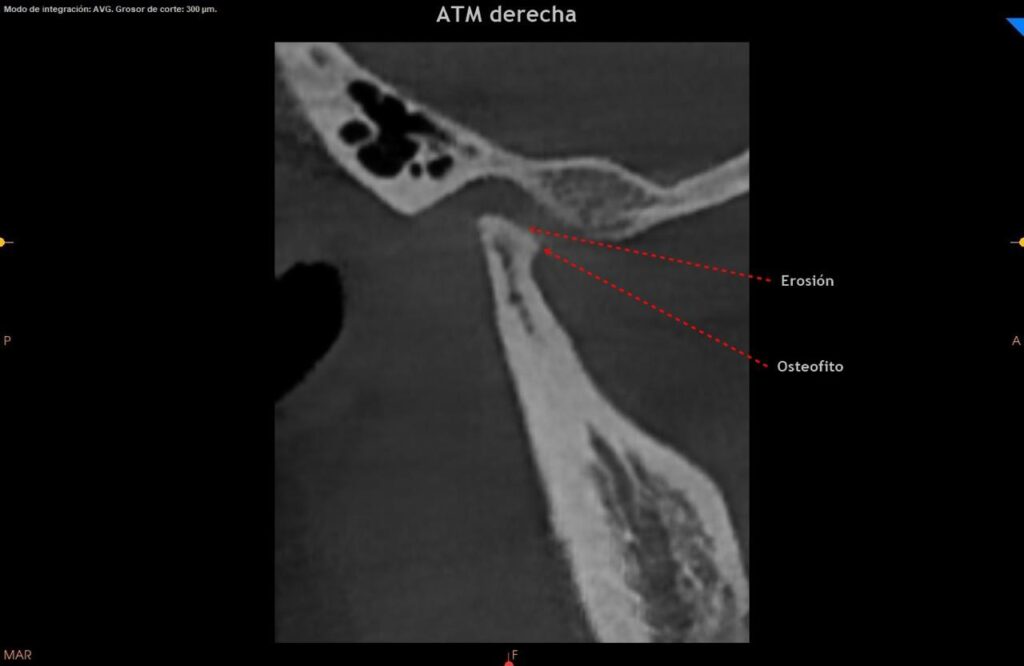

Evaluación médica y por imágenes:

Realizar una evaluación clínica completa y usar estudios de imagen (como rayos X, tomografía computarizada o resonancia magnética, para confirmar la presencia de osteofitos y evaluar su impacto en la articulación. -destacó la Dra. Mónica Souza Paz, quien está graduada de la UNAM y cuenta con un posgrado en ortodoncia y especialidad en dicho campo.